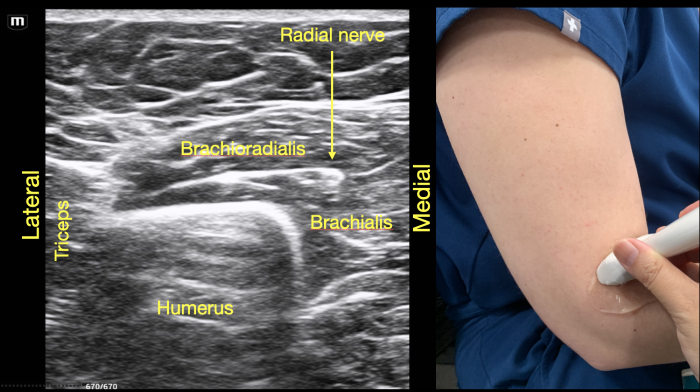

As the radial nerve is traced further distally, it can be seen leaving the spiral groove and wrapping around the anterior arm as it moves medially in between the brachioradialis and the brachialis muscle (Video Clip 2). The probe at this point is 3-4 cm above the elbow crease. This is the level that is blocked in the supracondylar UGRA. (Figure 5) A block at the supracondylar level will anesthetize the superficial and deep branch of the radial nerve as this branchpoint occurs distal to the elbow crease at the cubital fossa. The deep branch of the radial nerve continues between the brachioradialis and brachialis muscles, then passes through the supinator muscle emerging as the posterior interosseous nerve (PIN). The PIN provides motor innervation for the extensor muscles in the posterior compartment of the forearm as well as some sensory fibers to the dorsal wrist capsule. The superficial branch runs deep to the brachioradialis muscle then runs along the radial artery into the forearm, crossing over the snuffbox to the dorsum of the hand, and provides sensation to the dorsal hand and digits in the radial distribution.

RadialNerve-Image5 Aug2024.pngFigure 5. Supracondylar location of the radial nerve below the spiral groove